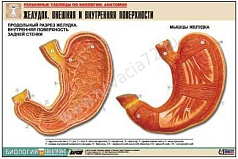

Комплект включает в себя 21 таблицу следующего содержания:

10. Желудок. Внешняя и внутренняя поверхность;